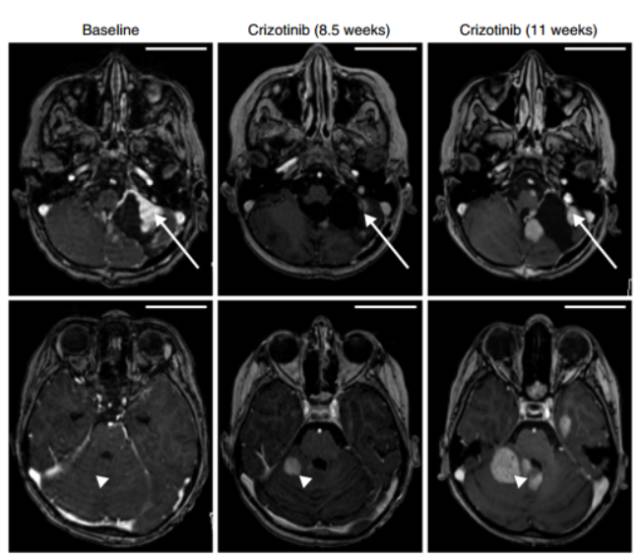

一名8岁的男孩,具有复发的小脑胶质母细胞瘤,伴随PTPRZ1-MET基因融合,使用MET抑制剂克唑替尼治疗后,11周内肿瘤显著减小(如右图上方长箭头所示),此位置症状缓解,但其他的位置发生新的耐药病灶(如右图下方三角箭头所示),由此可见综合治疗可能是达到持久临床获益的必经之路。

MET融合形式及MET抑制剂治疗效果